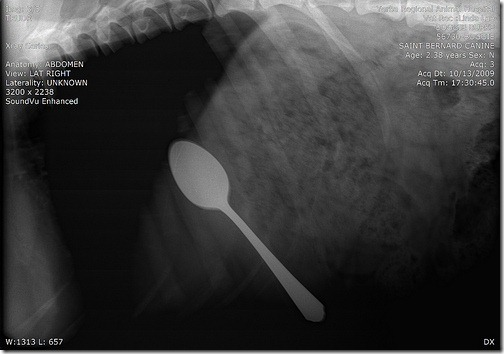

Ложка

Видимо собачка была настолько голодна, что съела ужин вместе с ложкой